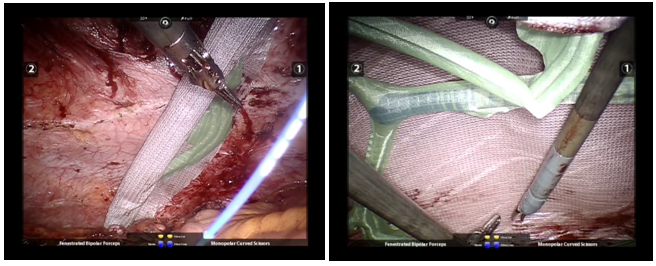

A left lateral approach is our usual technique both for a laparoscopic or a robotic repair. For the robotic procedure, the robot has to be positioned on the opposite side, ie on patient’s right in order to have correct ergonomy in the OR. Initial incision of 1 cm is usually extended by a few millimeters, especially in obese patients, because an open (Hasson) access to the abdomen is rather cumbersome. An opti-view trocar has been used in the past by the authors, but today it is avoided, especially in cases where abundant adhesions and altered anatomy is anticipated. After induction of the pneumoperitoneum, two 5mm trocars are inserted proximally and caudally to the camera port, along the midclavicular line (Figure 1). Adhesiolysis usually begins with greater omentum stuck on the anterior abdominal wall and then continues with the small bowel loops, especially if they are part of hernial sac content. Care is mandatory here, in order to minimize use of cautery, especially monopolar, to avoid bowel injury. Robotic stereoscopic 3D vision has been found by the authors to facilitate this challenging phase of the procedure. If bowel is injured during adhesiolysis, the authors prefer to repair the damage at the same time, rather than leaving it untreated for later. A serious perforation should raise the decision for conversion to laparotomy as well as avoiding the use of mesh. Sharp dissection is usually used with cutting down the adhesions by means of monopolar scissors. For blunt dissection the authors prefer to use a sponge held at the tip of a laparoscopic or robotic grasper (Figure 2). After completion of adhesiolysis and reduction of hernia content, a mesh is inserted and expanded with the help of assisting trocars. Self-expanding meshes (Figure 3) are quite practical in case of very large or multiple defects, because technical difficulty has been found to be proportional to the size of the defect and the necessary mesh. Fixation of the mesh takes place with absorbable or non-absorbable material. We usually avoid the use of drains. An exception was made for one of our cases with synchronous sleeve gastrectomy, where we used both an intraabdominal Jackson-Pratt suction drain, as well as a subcutaneous Redivac suction drain in the area of a very large umbilical hernia repair with excellent results. A patient with flank hernia was treated by extraperitoneal placement of a self-adherent mesh after extended dissection of the right lateral peritoneum.

Figure 2 Adhesiolysis and reduction of hernia content prior to repair in a patient with history of open distal pancreatectomy.

Figure 3 Use of self- expanding mesh in the same patient.